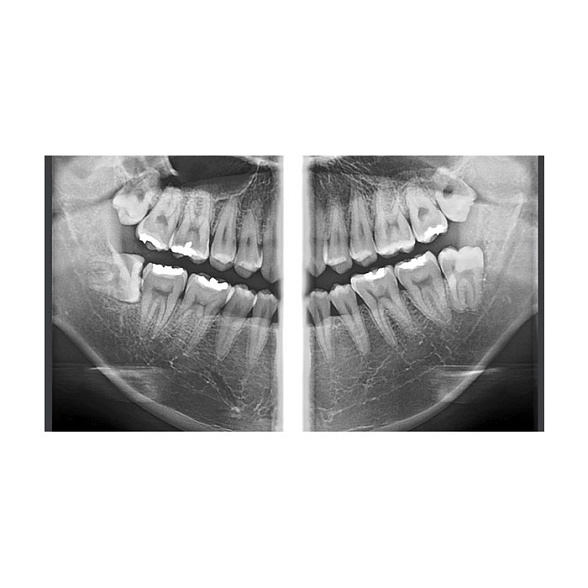

Veraview X800 P - комбинированная рентгеновская система высшего класса

Veraview X800 P: Комбинированная рентгеновская система для безупречной диагностики

Система Veraview X800 P представляет собой вершину технологий в области стоматологической визуализации. Это комбинированное решение, которое объединяет в себе возможности панорамной, цефалометрической и 3D-томографии, создавая универсальную диагностическую станцию высшего класса. Она разработана для клиник, которые стремятся предоставлять пациентам самый высокий уровень диагностики, планирования лечения и контроля его результатов.

Veraview X800 P — это не просто аппарат, это инвестиция в точность, эффективность и рост вашей клиники. Она позволяет проводить полный спектр рентгенологических исследований на одном устройстве, экономя пространство, время и бюджет, обеспечивая при этом бескомпромиссное качество изображений.

- Всесторонняя диагностика в одном аппарате: От панорамных снимков всей зубочелюстной системы до детальных 3D-томограмм отдельных сегментов и цефалометрического анализа для ортодонтии и ортогнатической хирургии. Больше нет необходимости направлять пациента в разные кабинеты или к сторонним специалистам.

- Высочайшее качество изображения: Цифровой плоскопанельный детектор с высоким разрешением обеспечивает исключительную четкость и детализацию. Это позволяет визуализировать мельчайшие анатомические структуры, ранние патологические изменения, точно оценивать состояние костной ткани, что критически важно для имплантации, эндодонтии и хирургии.

- Ортодонтия: Цефалометрический анализ для планирования лечения, оценка положения зубов и ретинированных клыков, контроль результатов.

- Терапия и эндодонтия: Диагностика скрытых кариозных полостей, анализ качества обтурации корневых каналов, выявление периапикальных изменений.

- Пародонтология: Оценка уровня костной ткани вокруг зубов, диагностика костных карманов.

Veraview X800 P — это комбинированная система. Помимо панорамных снимков, она позволяет делать цефалометрические снимки для ортодонтии и, что самое важное, получать объемные 3D-томограммы (КЛКТ). Это принципиально более высокий уровень диагностических возможностей.